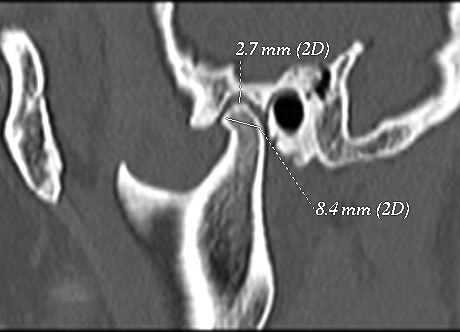

The temporomandibular joint (TMJ) is one of the most complex joints in the body and its harmonious functioning is very important to maintain a normal masticatory system. The morphologic alterations and the asymmetrical position of the TMJ structures may lead the various clinicalsigns & symptoms. Morphology of the temporomandibular joint may be influenced by gender of patients, environmental factor and also food habits at various places. Objective: To evaluate the morphology of the temporomandibular joint using computed tomography, in order to determine the condyle shape, joint space and glenoid fossa roof thickness. Material and Methods: One hundred and six healthy patients (212 TMJs) who visited a private hospital (or the University’s Hospital) for CT brain scan were included to this cross-sectional study sample.The patients were aged between 20–50 years with an average age of 35.46 years. All the images were taken by positioning patients in supine position with 120kvp , 50ma,2.33minute exposure with 0.7mm thick slicesby computed topography machine in all three projection that is Axial, Coronal and Saggital view. Results: For all variables, the mean and standard deviation were calculated, based on gender, and TMJ sides. The Paired t-test was used and P<0.05 will be considered to be significant. Conclusion: Present study showed that thereis positive evidence of temporomandibular joint involvement in elderly patients. Change in morphology and position of condylar head with glenoid fossa and roof thickness are one of the most common cause of degenerative diseases.